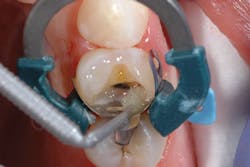

Figure 2: Selective enamel etching of tooth No. 12

After preparing the tooth, a viscous phosphoric acid gel was carefully traced around the margins of the preparation for a selective enamel etching technique and allowed to react for 15 seconds (figure 2). This was followed by copious water rinsing. Isolation was achieved using the Palodent Plus Sectional Matrix System (Dentsply Sirona), and Prime&Bond Elect was scrubbed over the entire preparation of tooth No. 12 followed by a gentle stream of oil-free air for five seconds to thin the material and evaporate the acetone solvent (figure 3).